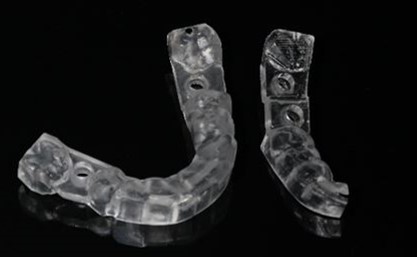

微創植牙三步驟:

- 術前依照骨頭狀況評估植牙角度及位置

- 結合 3D電腦斷層影像分析,制訂詳細手術治療計畫,提前確定植牙深度、尺寸。讓手術過程中降低手術風險且大幅度提升植牙成功率

- 手術過程使用3D列印的高精準度導引板,不只增加手術的穩定性、安全性,減小手術傷口,減少疼痛,讓術後傷口復原時間更短,不影響日常生活及工作。